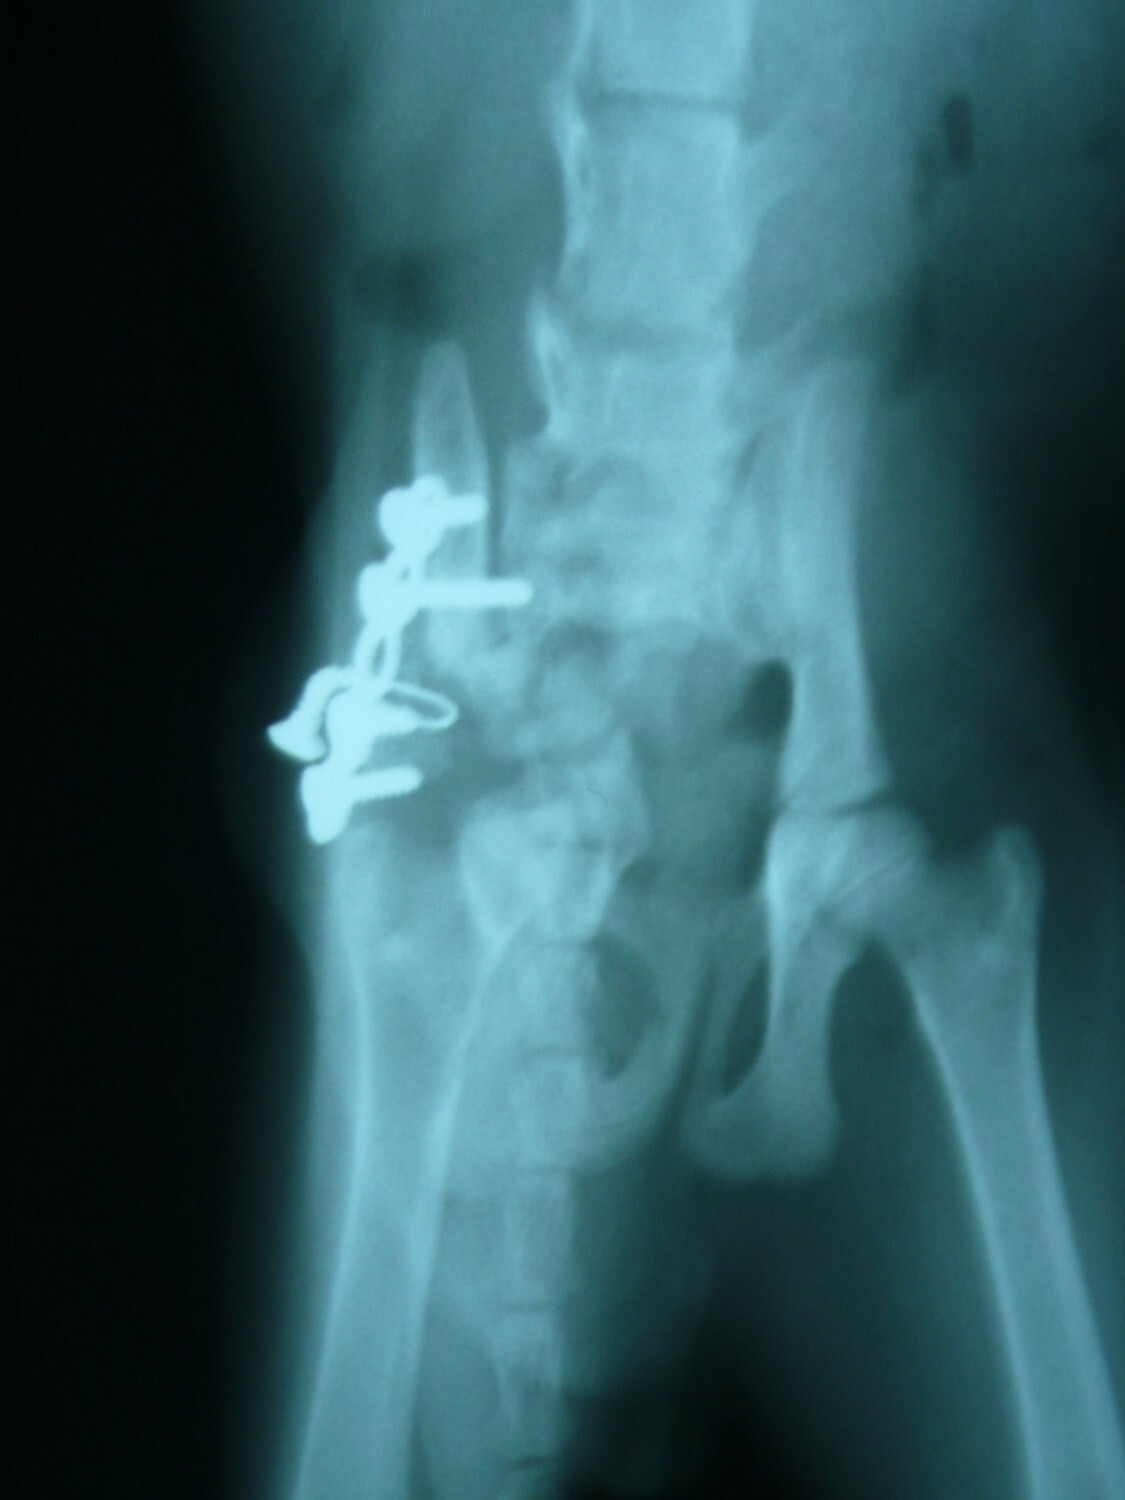

主題: 大龍街骨盤骨折橘白貓第二次醫療 申請者姓名: Akimasa Tu 花色: 申請日期: 2013-01-10 01:15:09 申請者部落格: 申請者臉書網址: https://www.facebook.com/akimasa.tu 所在縣市/合作醫院: 台北市/長沁動物醫院 治療費用: 10000元 需求人數: 22人 已結案 (2013-02-23 11:57:47) 報名人員: Julling Hu(已付款)、speciallucky(已付款)、Mau Lin(已付款)、阿麥麥(已付款)、李安妮(已付款)、Lichen Cheng(已付款)、J2(已付款)、Diamond Wu(已付款)、Monica Hu(已付款)、孫小晴(已付款)、Joyce Shih(已付款)、Lynn Lin(已付款)、Ray Lei(已付款)、Chinling Ho(已付款)、Shirley(已付款)、Shirley(已付款)、fenny(已付款)、yun(已付款)、yun(已付款)、yun(已付款)、yun(已付款)、yun(已付款)、 候補人員: 然後勒、 動物病情說明: 這隻是在大同區大龍街被救援的小貓,疑似被狗咬傷的小貓,之前因為

骨盤骨折,無法排便,而進行手術,術後先帶回照顧,原本食欲及活動

力都很正常,但一段時間後,看他常常好貓砂,但又沒大便,幾天後不

吃東西,帶回原手術醫院檢查,發現他肚子又是大便,而且手術固定的

骨板,螺絲鬆脫了!

可能是腸子蠕動不良,或鬆脫螺絲導致無法排便,因骨盤已固定,所以

院方決定將鬆脫螺絲及骨板再次開刀移除,術後活動力及食欲又恢復正

常,目前又先帶回照顧,因同時間又另一隻小貓得了貓瘟,為求保險起

見,也一並幫他注射了第一劑的三合一疫苗。